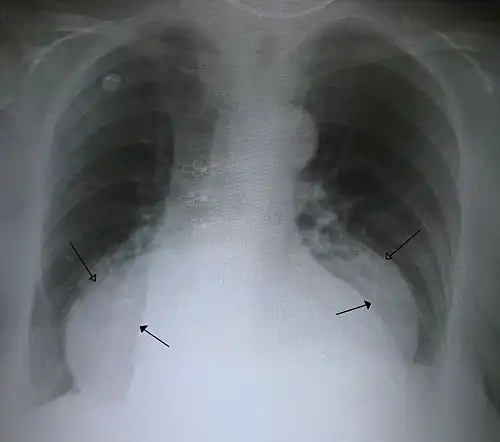

The diagnosis of a hiatal hernia is typically made through an upper GI series, endoscopy, high resolution manometry, esophageal pH monitoring, and computed tomography (CT). Barium swallow, as in the upper GI series, allows the size, location, stricture, and stenosis of oesophagus to be seen. It can also evaluate the oesophageal movements. Endoscopy can analyse the esophageal internal surface for erosions, ulcers, and tumours.

Meanwhile, manometry can determine the integrity of esophageal movements and the presence of esophageal achalasia. pH testing allows the quantitative analysis of acid reflux episodes. A CT scan is useful in diagnosing complications of hiatal hernia, such as gastric volvulus, perforation, pneumoperitoneum, and pneumomediastinum.[8]